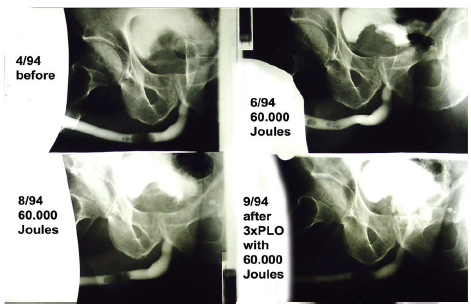

used 1993 this set for Coagulation of prostate. With 40Wcw

NdYAG we burned non contact mode into every treatment point

1000 Joules in a grid of about 5mm. Our fibres made a slump

from about 500 USD to 1 USD and we were faster as ILCP. Real

problem was publishing this experiment. Belgian Colleagues helped us at the 7thVideo Urology

World Congress/-Antwerp June 1996:Our equipment made a

5-8mm- diameter coagulation cylinder with a depth of about 1,4 cm so big adenoma needs more sessions. But it was the lowest

complication rate we ever had in 391 cases besides fever only

7xdirect bleedings lasering directly at micturation failure and 4x

necrotic tissue as micturation failure. We looked for better techniques. They had specific